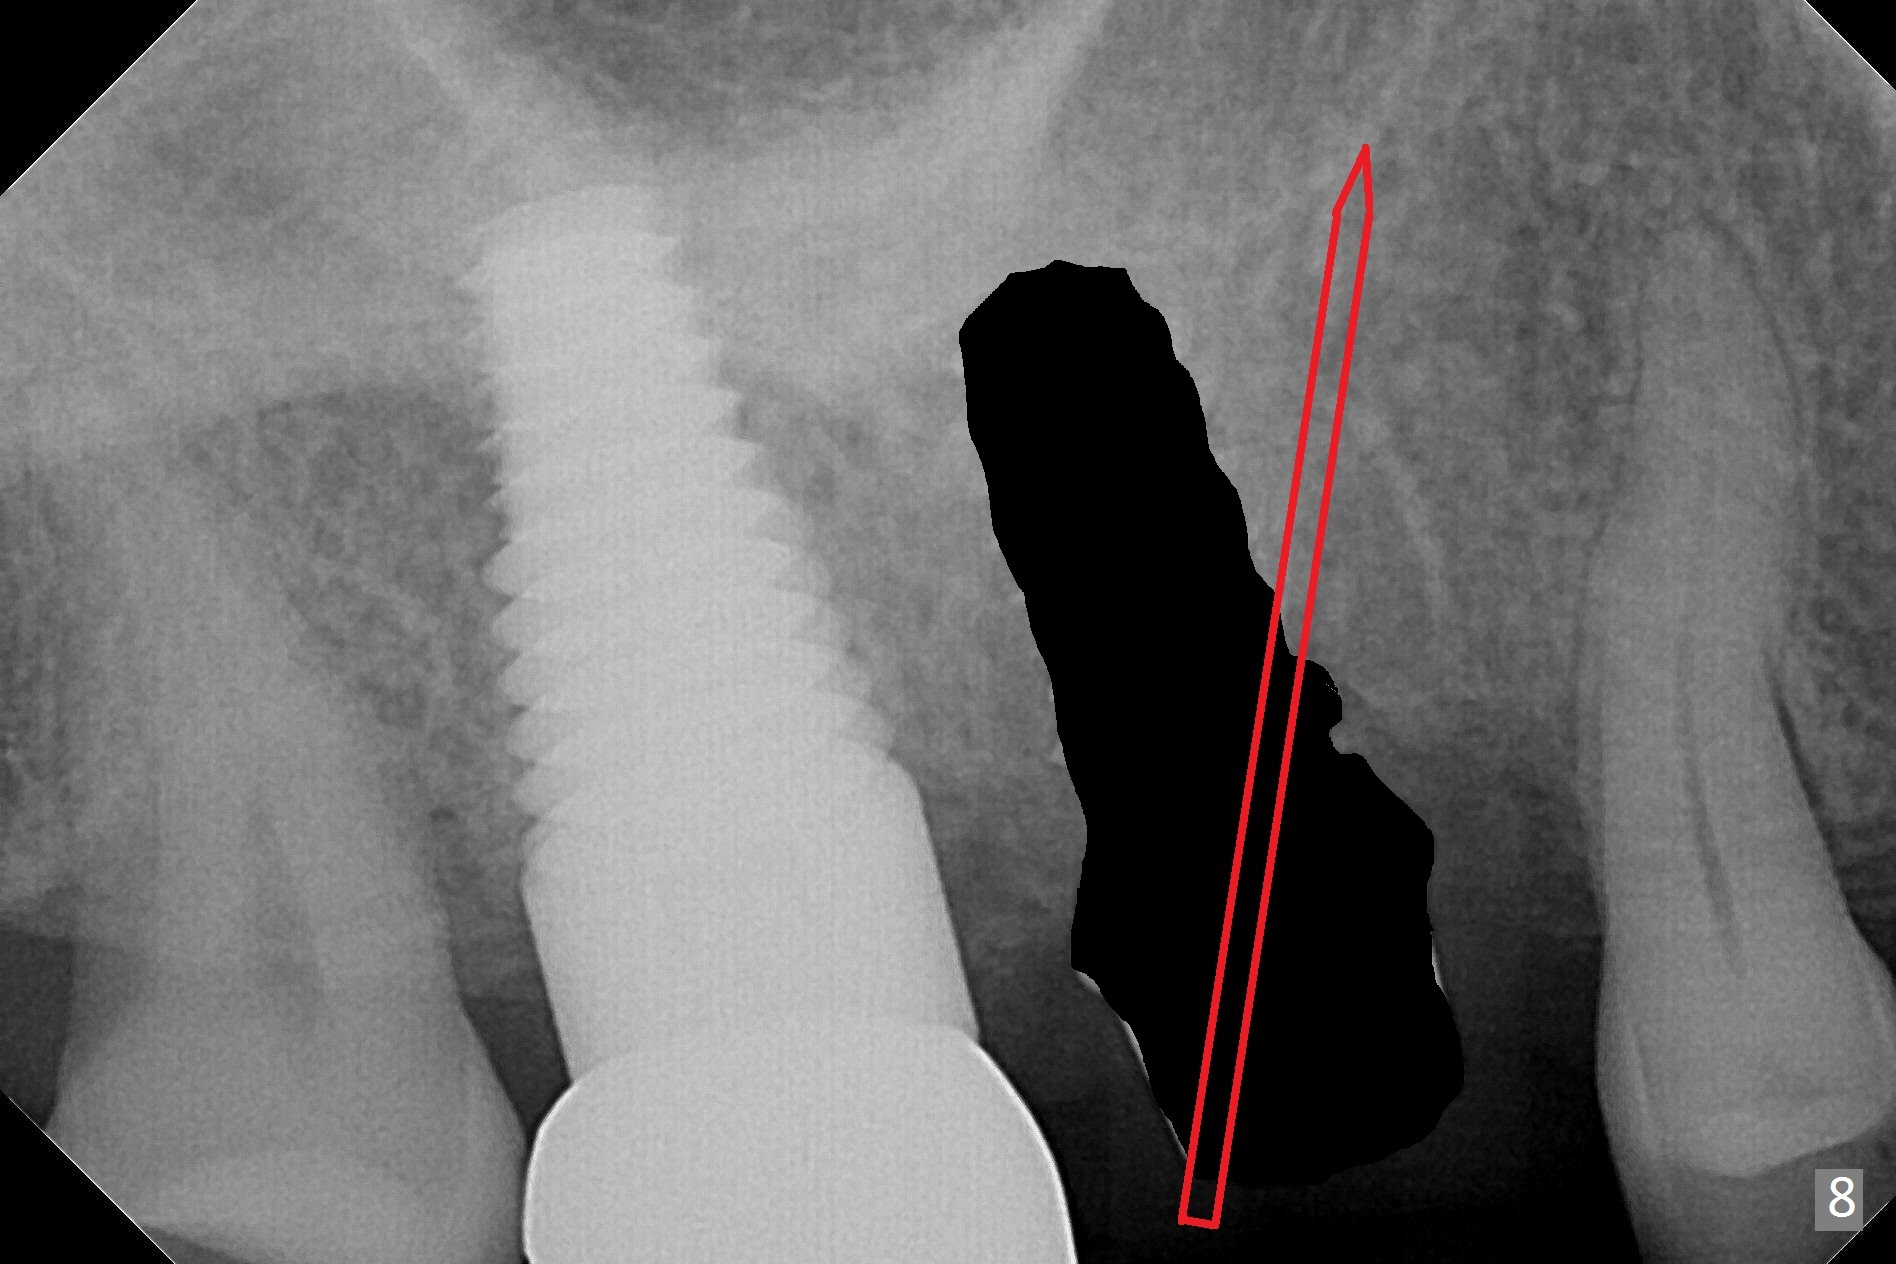

Heavy bruxism is characterized by the crack at #3 (symptomatic, requiring emergency extraction) and loss of the palatal cusp at #5 (Fig.1). Osteotomy is initiated in the septal slope (Fig.2 S) with a 1.6 mm pilot drill for 9 mm (with sudden empty feeling), followed by Marking bur. After 4.3 mm Magic Drill is used for ~ 9 mm, the sinus membrane is found to perforate. A dummy implant (5x9 mm, 2 mm shorter than design) is placed short of the sinus floor (Fig.3 ^). Prior to placement of 5.5x9 mm IBS implant (~ 35 Ncm, Fig.4,5), a piece of Osteogen plug is inserted into the osteotomy for repair of the perforation. The final implant is also shy of the sinus floor (Fig.5 ^). The Osteogen plug is apparently placed underneath the sinus floor so that it should be able to repair hard and soft tissue defects. The remaining sockets are mainly filled with Osteogen plug, while the implant plateau is covered by autogenous bone and Osteogen. When a 6.5x4(3) mm abutment is placed, an immediate provisional is fabricated (Fig.6) with its margin placed subgingival (Fig.6 inset dashed line). This innovative design of the provisional is to prevent collapse of the most coronal gingiva and loss of bone graft, particularly where the bony plate is defective. Although there is mild pain postop, nasal hemorrhage or discharge is absent.